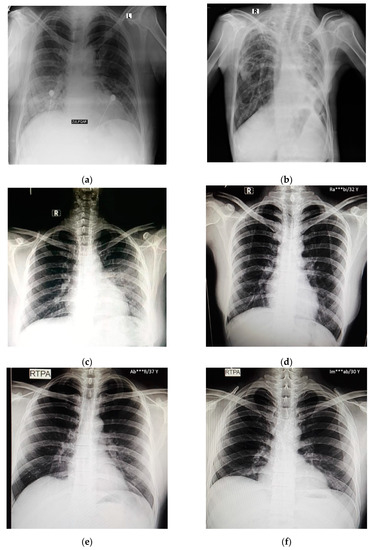

In this study, pulmonary (chest) X-ray images were used for the diagnosis of COVID-19. The dataset was categorized into two main classes, i.e., COVID-19 and normal. A total of 7232 images (3616 COVID-19 + 3616 normal) were accessed from the ‘COVID-19 Radiography Database (available at Kaggle, https://www.kaggle.com/tawsifurrahman/covid19-radiography-database, accessed on 4 May 2021) [30]. From the total images, 70% (5062 images) were used for training + validation, and the remaining 30% (2170 images) were used for testing purposes. The training + validation dataset of 5062 images was further split into a 70:30 ratio, i.e., 3544 (70%) images for training purposes and 1518 (30%) images for validation purposes. The details of the data splitting are given in Table 1. In addition to the dataset accessed via Kaggle, another locally collected dataset of 450 images (COVID-19 + normal) was also used for testing and prediction purposes. This indigenous data of chest X-ray images of Pakistani COVID-19 positive and normal patients have been collected from a local hospital. The samples of normal and COVID-19 X-ray images assessed via the Kaggle database are shown in Figure 1, whereas the samples of the locally collected images are given in Figure 2.

Figure 1.

Samples of chest X-ray images assessed via Kaggle database [30,31,32] for training purposes: (a–c) normal chest X-rays; (d–f) COVID-19 chest X-rays.